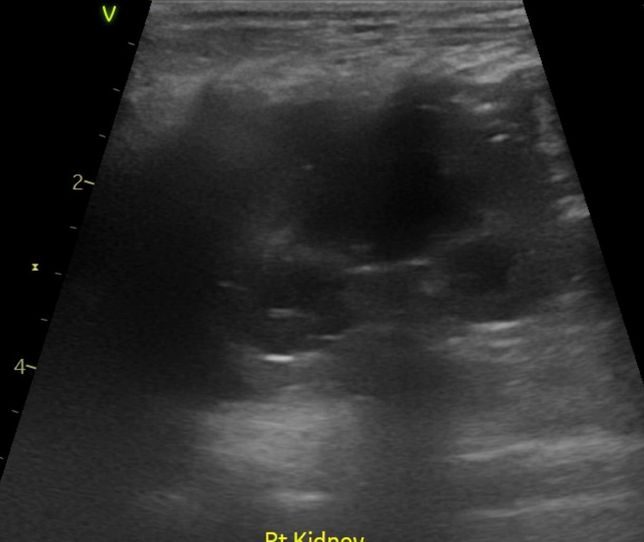

- 반려동물 건강반려동물Q. 강아지 신장결석 칼슘옥살 스트루바이트 둘중 어느것 같아보이는지요?강아지 신장결석 칼슘옥살 스트루바이트 둘중 어느것 같아보이는지요? 그냥 보시기에 만약에 판별이 가능하다면 알려주심 정말 감사하겠습니다. 병원만 3곳 다녔고 소변검사에 방광천자 제외하고 전부다 해봤는데 현재 6개월이 넘어갔는데 무슨 결석인지도 모르는 상태고 결석 크기는 신장 양쪽에 점점 커지고 있는 상황이라 이대로는 가만 있을수가 없어서 이렇게나마 질문글 올립니다.. 부디 알려주심 정말 한생명 살리는샘치고 정말 감사하겟습니다.